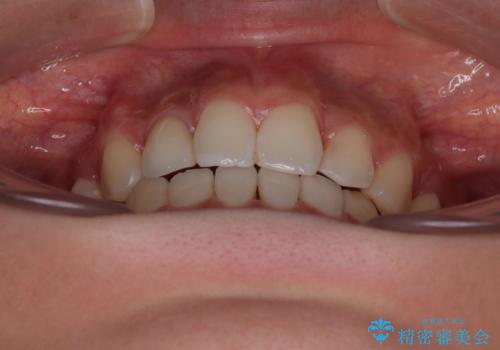

- 前歯のデコボコと口元の突出感を気にして来院された患者様です。

口元の突出感が認められ、更には左右で異なる咬合状態であったため、下顎右側は第二小臼歯を、左側は第一小臼歯を抜去することでバランスを取るような治療計画としました。

また上顎前歯は大臼歯に補綴治療が必要であったため、矯正治療後にオールセラミッククラウンによる補綴治療を行うこととしました。

下顎の抜歯位置を左右で変えることで、最終的に上下正中をほぼ一致させることができました。